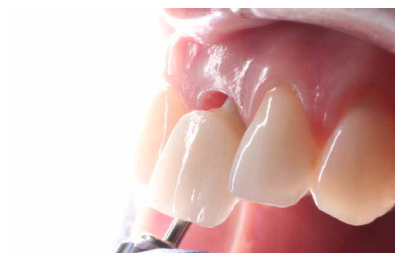

La fluorosis dental es una condición irreversible originada durante el desarrollo dental que genera pigmentaciones intrínsecas, alteraciones en el esmalte manifestadas a manera de manchas blancas, amarillas o marrones, que perjudican la estética y repercuten en el desenvolvimiento social. El presente reporte de caso clínico describe la combinación de los procedimientos de microabrasión y blanqueamiento dental, como alternativas en la eliminación de pigmentaciones dentales. Después del diagnóstico de la patología, verificación de ausencia de lesiones pulpares y caries, una explicación minuciosa a la paciente y obtención del consentimiento informado, se realizó limpieza de las superficies dentales y, bajo aislamiento absoluto, se procedió a realizar la técnica de microabrasión mediante ácido clorhídrico al 6,6% siguiendo las instrucciones del fabricante. Concluido el procedimiento y, observando que era posible mejorar aún más la estética, se decidió ejecutar el procedimiento de blanqueamiento dental, a base de peróxido de hidrógeno al 40% en el consultorio, seguido por peróxido de carbamida al 10% aplicado en el domicilio. Al finalizar el tratamiento se observó uniformidad en el color dental, conjugados con una evidente mejora en la calidad de vida y relación social de la paciente.

La combinación de procedimientos, como el reportado en este caso, constituye una excelente alternativa de tratamiento para eliminar pigmentaciones fluoróticas moderadas.